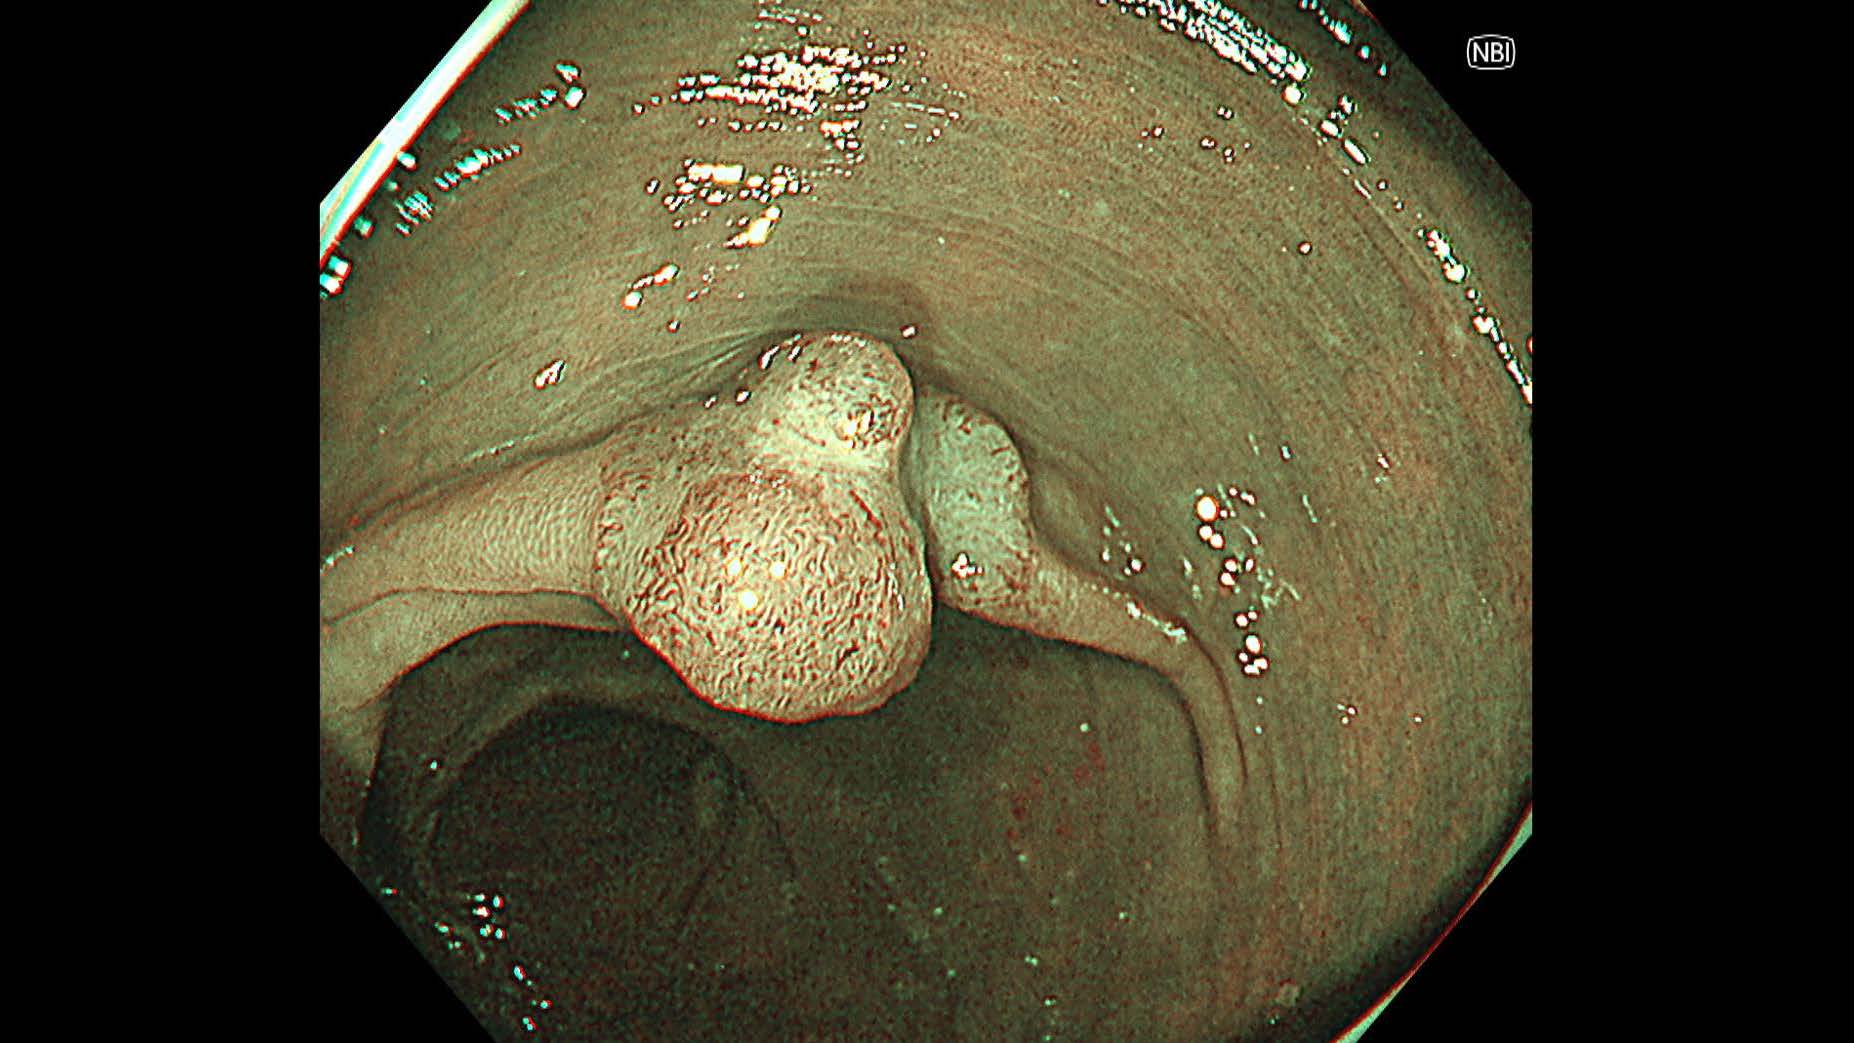

消化管Mapping~大腸~ 2025.6.11

内視鏡検査・治療

消化管Mapping